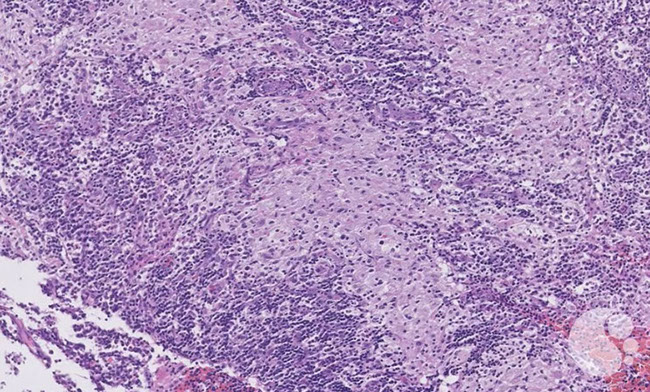

Reactive paracortical hyperplasia [3]. Hyperplasia of the paracortex outside of follicles. Can have vaguely nodular areas of enlargement of the paracortex. The T-cells appear monomorphous, small and mature appearing. Have almost evenly-spaced scattered interdigitating dendritic cells sprinkled throughout that gives it a mottled-effect

Kikuchi-Fujimoto disease [3] - Classic low-power appearance with reactive follicles at the periphery and paracortical expansion.

Kikuchi-Fujimoto disease [3]